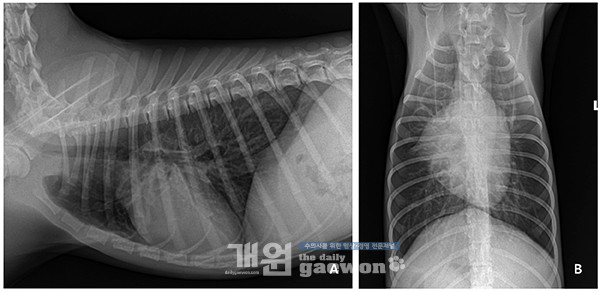

호흡음과 함께 활력 징후의 개선이 있었고, 일반 방사선 상에서도 우측 중엽의 미약한 폐포침윤 소견을 제외하고는 폐 전반적으로 보였던 기관지 패턴과 간질 패턴이 눈에 띄게 개선됨을 확인할 수 있었다[그림 2].